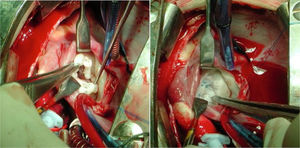

El segundo paciente fue un adulto de 66 años, operado en la infancia de un cierre de la comunicación interauricular. Presentaba una alta incidencia familiar de cardiopatía congénita sin aislamiento de un sustrato genético. Tenía una IM grado iv por restricción del velo posterior con un anillo mitral de 64mm y una IT grado ii con anillo tricuspídeo de 47mm. Se realiza una plastia mitral con anillo de CG Future® de 36mm (Medtronic) con implante de neocuerda en segmento A1 y una anuloplastia tricuspídea con anillo Contour 3D® de 36mm (Medtronic). Presenta bloqueo auriculoventricular completo en el postoperatorio inmediato, por lo que se implanta un marcapasos definitivo al sexto día postoperatorio. A las 24h de la intervención se realiza un cateterismo de urgencia por infarto postoperatorio. Se objetiva acodamiento de la coronaria derecha debido a un punto del anillo tricúspide. Dado que la repercusión solo era bioquímica, sin alteración en la contractilidad, se decide tomar una actitud conservadora y el paciente evoluciona de manera satisfactoria. No obstante, a los 20 días de la intervención el paciente presenta de manera súbita disnea y ortopnea. Se objetiva dehiscencia de la porción posterior del anillo mitral (fig. 1), por lo que se interviene de urgencia implantando una prótesis mitral mecánica Carbomedics® 31mm.

El futuro de la cirugía de reparación valvular múltiple en los pacientes con cardiopatía congénita es incierto. Hay debate sobre el material y las técnicas a emplear. Idealmente no hay que emplear material protésico que degenera con el tiempo y no crece, e intentar trabajar con el tejido autógeno siempre que sea posible. En nuestro caso, ha sido frecuente emplear varias técnicas distintas para reparar una misma válvula5,6,12,14. Este tipo de reparaciones difiere de los cánones habituales de la reparación de valvulopatías adquiridas. En el caso de los defectos de los cojinetes endocárdicos, habitualmente no empleamos anillos protésicos para la válvula mitral. Los defectos de este estilo se corrigen bien cerrando el cleft mitral y a veces es preciso asociar una comisuroplastia. La arquitectura de las válvulas auriculoventriculares de estos pacientes está alterada, y comparado con la anatomía habitual, un anillo protésico distorsiona la plastia mitral15,16. El abordaje cambia cuando la etiología de la valvulopatía mitral es una displasia primaria no asociada a defecto del septo auriculoventricular; aquí la reparación es más compleja, requiriendo diversas técnicas para conseguir una buena coaptación de los velos. En este tipo de pacientes sí es necesario asociar un anillo mitral para consolidar la reparación, siempre y cuando el tamaño del paciente nos lo permita (fig. 2). En la válvula tricúspide se emplea más libremente el anillo o, en su defecto, una plastia de Vega cuando el paciente es pediátrico. En el caso de la válvula aórtica recomendamos afeitado de velos y apertura de comisuras en válvulas estenóticas para ganar movilidad, aunque el arsenal terapéutico para anillos pequeños es más limitado (fig. 3). En los casos de insuficiencia aórtica se hará plastia de velos para evitar que estos prolapsen y logren una buena altura de coaptación, y si esta se asocia a dilatación aneurismática de la raíz aórtica se realizará técnica de David. Cuando la valvuloplastia convencional no es suficiente hay que explantar la válvula, teniendo como principal opción el Ross en lactantes y niños pequeños. Nuestra experiencia inicial con la técnica de Ozaki (reconstrucción de neovelos aórticos) es buena y puede tener un papel en los candidatos que requieran la reparación de 2 o más válvulas13.